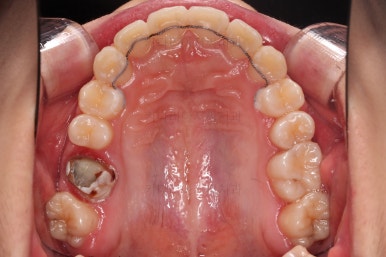

연산동치과 초진 시, 입안의 모습입니다.

보시다시피 앞니쪽이 많이 삐뚤고요. 어금니쪽이 긴밀하지 못한 부정교합이 있네요.

그리고 왼쪽 하단의 사진에 화살표를 보시면, 예전에 신경치료를 해둔 치아인데 어린 나이에 신경치료를 하다보니 크라운으로 치료를 마무리 하지 못했어요.